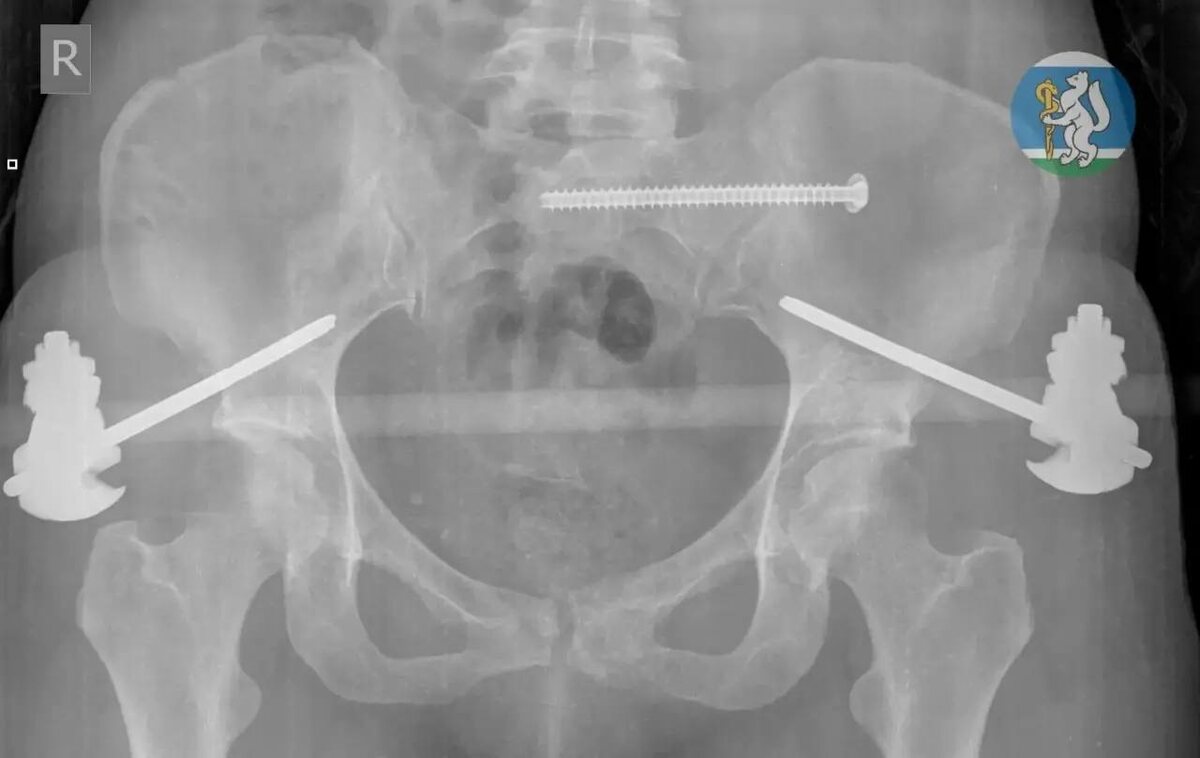

36-лСтняя ΠΆΠΈΡ‚Π΅Π»ΡŒΠ½ΠΈΡ†Π° Π•ΠΊΠ°Ρ‚Π΅Ρ€ΠΈΠ½Π±ΡƒΡ€Π³Π° ΡƒΠΏΠ°Π»Π° с сСдьмого этаТа, ΠΊΠΎΠ³Π΄Π° ΠΌΡ‹Π»Π° ΠΎΠΊΠ½Π°. Π’ состоянии Ρ‚ΡΠΆΠ΅Π»Π΅ΠΉΡˆΠ΅Π³ΠΎ травматичСского шока Π΅Ρ‘ доставили Π² Π“ΠΎΡ€ΠΎΠ΄ΡΠΊΡƒΡŽ Π±ΠΎΠ»ΡŒΠ½ΠΈΡ†Ρƒ β„–36 «ВравматологичСская», Π³Π΄Π΅ Π²Ρ€Π°Ρ‡ΠΈ диагностировали Ρ‡Π΅Ρ€Π΅ΠΏΠ½ΠΎ-ΠΌΠΎΠ·Π³ΠΎΠ²ΡƒΡŽ Ρ‚Ρ€Π°Π²ΠΌΡƒ, ΠΏΠΎΠ²Ρ€Π΅ΠΆΠ΄Π΅Π½ΠΈΠ΅ ΠΏΠΎΠ·Π²ΠΎΠ½ΠΎΡ‡Π½ΠΈΠΊΠ°, мноТСствСнныС ΠΏΠ΅Ρ€Π΅Π»ΠΎΠΌΡ‹ Ρ‚Π°Π·Π° ΠΈ ΠΎΡ‚ΠΊΡ€Ρ‹Ρ‚Ρ‹Π΅ ΠΏΠ΅Ρ€Π΅Π»ΠΎΠΌΡ‹ Π½ΠΎΠ³ΠΈ. Π‘ΠΎΠ»ΡŒΡˆΠΈΠ½ΡΡ‚Π²ΠΎ ΠΏΠΎΡΡ‚Ρ€Π°Π΄Π°Π²ΡˆΠΈΡ… с Ρ‚Π°ΠΊΠΈΠΌΠΈ Ρ‚Ρ€Π°Π²ΠΌΠ°ΠΌΠΈ Π½Π΅ Π΄ΠΎΠΆΠΈΠ²Π°ΡŽΡ‚ Π΄ΠΎ ΠΏΡ€ΠΈΠ΅Π·Π΄Π° скорой.

πŸ§‘ НСсколько часов Π±Ρ€ΠΈΠ³Π°Π΄Π° Ρ…ΠΈΡ€ΡƒΡ€Π³ΠΎΠ², Ρ‚Ρ€Π°Π²ΠΌΠ°Ρ‚ΠΎΠ»ΠΎΠ³ΠΎΠ², Π½Π΅ΠΉΡ€ΠΎΡ…ΠΈΡ€ΡƒΡ€Π³Π° ΠΈ Ρ€Π΅Π°Π½ΠΈΠΌΠ°Ρ‚ΠΎΠ»ΠΎΠ³Π° Π±ΡƒΠΊΠ²Π°Π»ΡŒΠ½ΠΎ Π²Ρ‹Ρ€Ρ‹Π²Π°Π»Π° ΠΆΠ΅Π½Ρ‰ΠΈΠ½Ρƒ с Ρ‚ΠΎΠ³ΠΎ свСта. Π Π°Π±ΠΎΡ‚Π° шла поэтапно: сначала рСанимация, Π·Π°Ρ‚Π΅ΠΌ стабилизация, ΠΏΠΎΡ‚ΠΎΠΌ β€” сСрия ΠΎΠΏΠ΅Ρ€Π°Ρ†ΠΈΠΉ. Бпустя мСсяц ΠΏΠ°Ρ†ΠΈΠ΅Π½Ρ‚ΠΊΡƒ выписали Π² ΡƒΠ΄ΠΎΠ²Π»Π΅Ρ‚Π²ΠΎΡ€ΠΈΡ‚Π΅Π»ΡŒΠ½ΠΎΠΌ состоянии, ΠΈ сСгодня ΠΎΠ½Π° ΠΏΡ€ΠΎΡ…ΠΎΠ΄ΠΈΡ‚ Ρ€Π΅Π°Π±ΠΈΠ»ΠΈΡ‚Π°Ρ†ΠΈΡŽ.